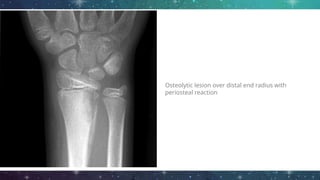

Imaging

● Plain film radiography

○ Extend at least 1cm/ compromise 30 -

50% of bone mineral

○ Bone destruction may not appear until

approximately 2 weeks after onset

○ Osteolysis, periosteal reaction and

sequestra

Osteolytic lesion over distal end radius with

periosteal reaction